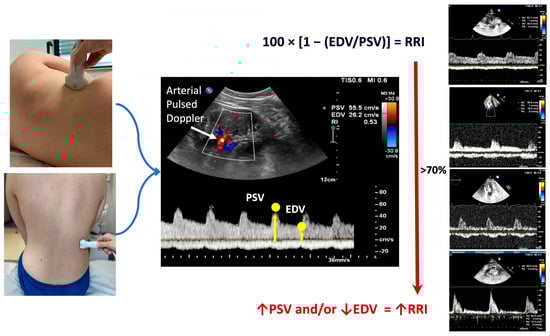

2. Methodological Aspects of Renal Doppler Evaluation